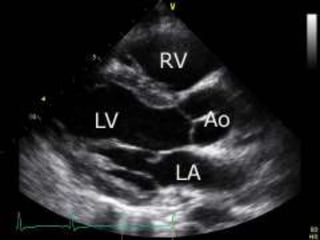

Ecocardiografia

 CIV

 Obstrução do trato de saída ventricular direita

DIAGNÓSTICO

• #23 Observar o defeito do septo e o cavalgamento da aorta